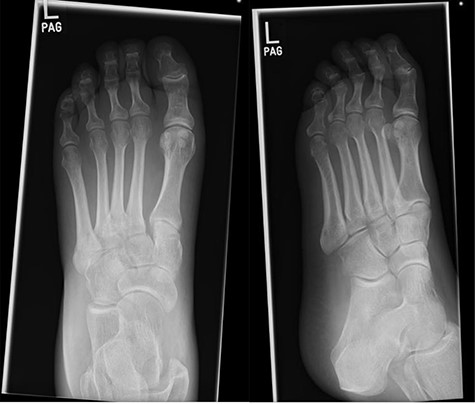

Foot X-rays taken at acute presentation (AP and lateral views), demonstrating rapid interval progression and destruction to mid-foot.

At this presentation, plain film X-ray revealed complete fracture dislocations of the second to fifth tarsometatarsal joints, involving the lateral, middle and medial cuneiform bones of the left mid-foot (Lisfranc fracture dislocations; Fig. 3). This was correlated with bone CT (computed tomography) and MR (magnetic resonance) imaging, with interval changes noted to be of rapid onset (Fig. 4).